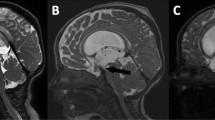

The flow void phenomenon near the third ventricle was classified into four categories, both in groups I and II for all sequences: grade 0 (no flow void in the interpeduncular cistern, through the floor of the third ventricle or inside the third ventricle); grade 1 (flow void in only one of them); grade 2 (flow void in two of them); grade 3 (flow void in all of them) (Figs. 1 and 2).

a There is no clear signal void through the floor of the third ventricle in a patient with ETV in the midsagittal image of 5 mm thickness sagittal TSE. Flow void is graded as grade 0. b There is signal void only in the interpeduncular and prepontine cisterns, not through the floor of the third ventricle and inside the third ventricle in a patient evaluated for hydrocephalus prior to surgery. Flow void is graded as grade 1 in sagittal 2 mm TSE T2. c A patient with communicant hydrocephalus after ETV demonstrates flow through the floor of the third ventricle and prepontine cistern in 2 mm sagittal TSE T2 with flow compensation. Flow void is graded as grade 3. d There is extensive flow void graded as grade 3 through the fenestration in sagittal TSE T2 without flow compensation

a 5 mm sagittal TSE T2 obtained 12 months after ETV demonstrates surgical defect in the floor of the third ventricle of a 22-month-old boy with communicant hydrocephalus. Although there is slight heterogeneity in the interpeduncular cistern and the third ventricle, flow void is not seen as definite hypointensity in them. Flow void is graded as grade 0 in midsagittal 5 mm sagittal TSE T2, b 5 mm axial TSE T2 through the interpeduncular cistern demonstrates extensive signal void in the interpeduncular cistern. As flow void also is seen in two consecutive slices through the floor of the third ventricle and in the third ventricle (not shown), it is graded as grade 3, c 3 mm coronal TSE T2 demonstrate grade 2 flow void as seen in the third ventricle and through the fenestration, but not in the interpeduncular cistern, d sag 3D CISS demonstrates no flow void in cisterns, through the fenestration and in the third ventricle. It is graded as grade 0, e 2 mm sagittal TSE T2 with flow compensation shows flow void obviously in the third ventricle and through the fenestration. It is graded as grade 2, and f 2 mm sagittal TSE T2 without flow compensation shows extensive grade 3 flow void in the interpeduncular cistern, through the fenestration and in the third ventricle